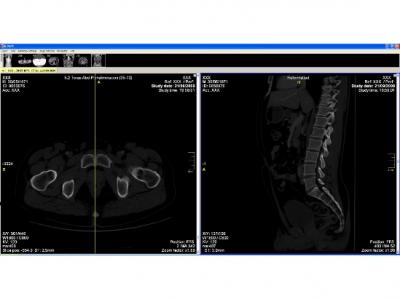

image: The picture on the left shows a horizontal section across the symphysis of the pubis. The picture on the right shows a sagittal section across the right symphysis surface. view more

The researchers examined the sagittal sections of the the articular surface of the pubic symphysis and the pubis itself, thus obtaining four sections: two sections of the right and left symphysis, and two sections of the pubis. Imaging techniques were used to analyze sections, histograms of the structures were obtained and the statistical variables of histograms were entered into the Image program to determine how histograms are related to age and sex.